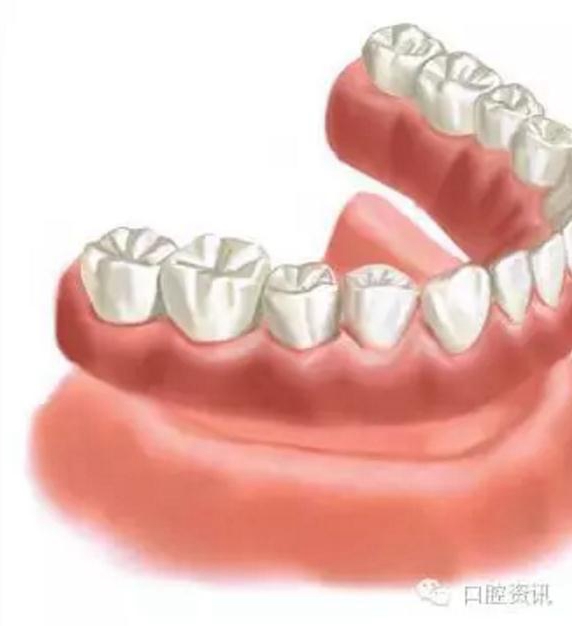

4 . 全口義齒

傳統(tǒng)的全口義齒利用牙床和黏膜提供固位力。而當天然牙缺失后, 牙槽骨會逐漸吸收, 這會影響義齒的穩(wěn)定度, 進一步會影響您的咀嚼功能和舒適感。義齒可能需要反復調(diào)改才能達到滿意的效果。這種情形下, 通過種植體支持全口義齒, 可以有效地提高義齒的固位力。

9.jpg

圖9. 傳統(tǒng)的全口義齒 (活動假牙)